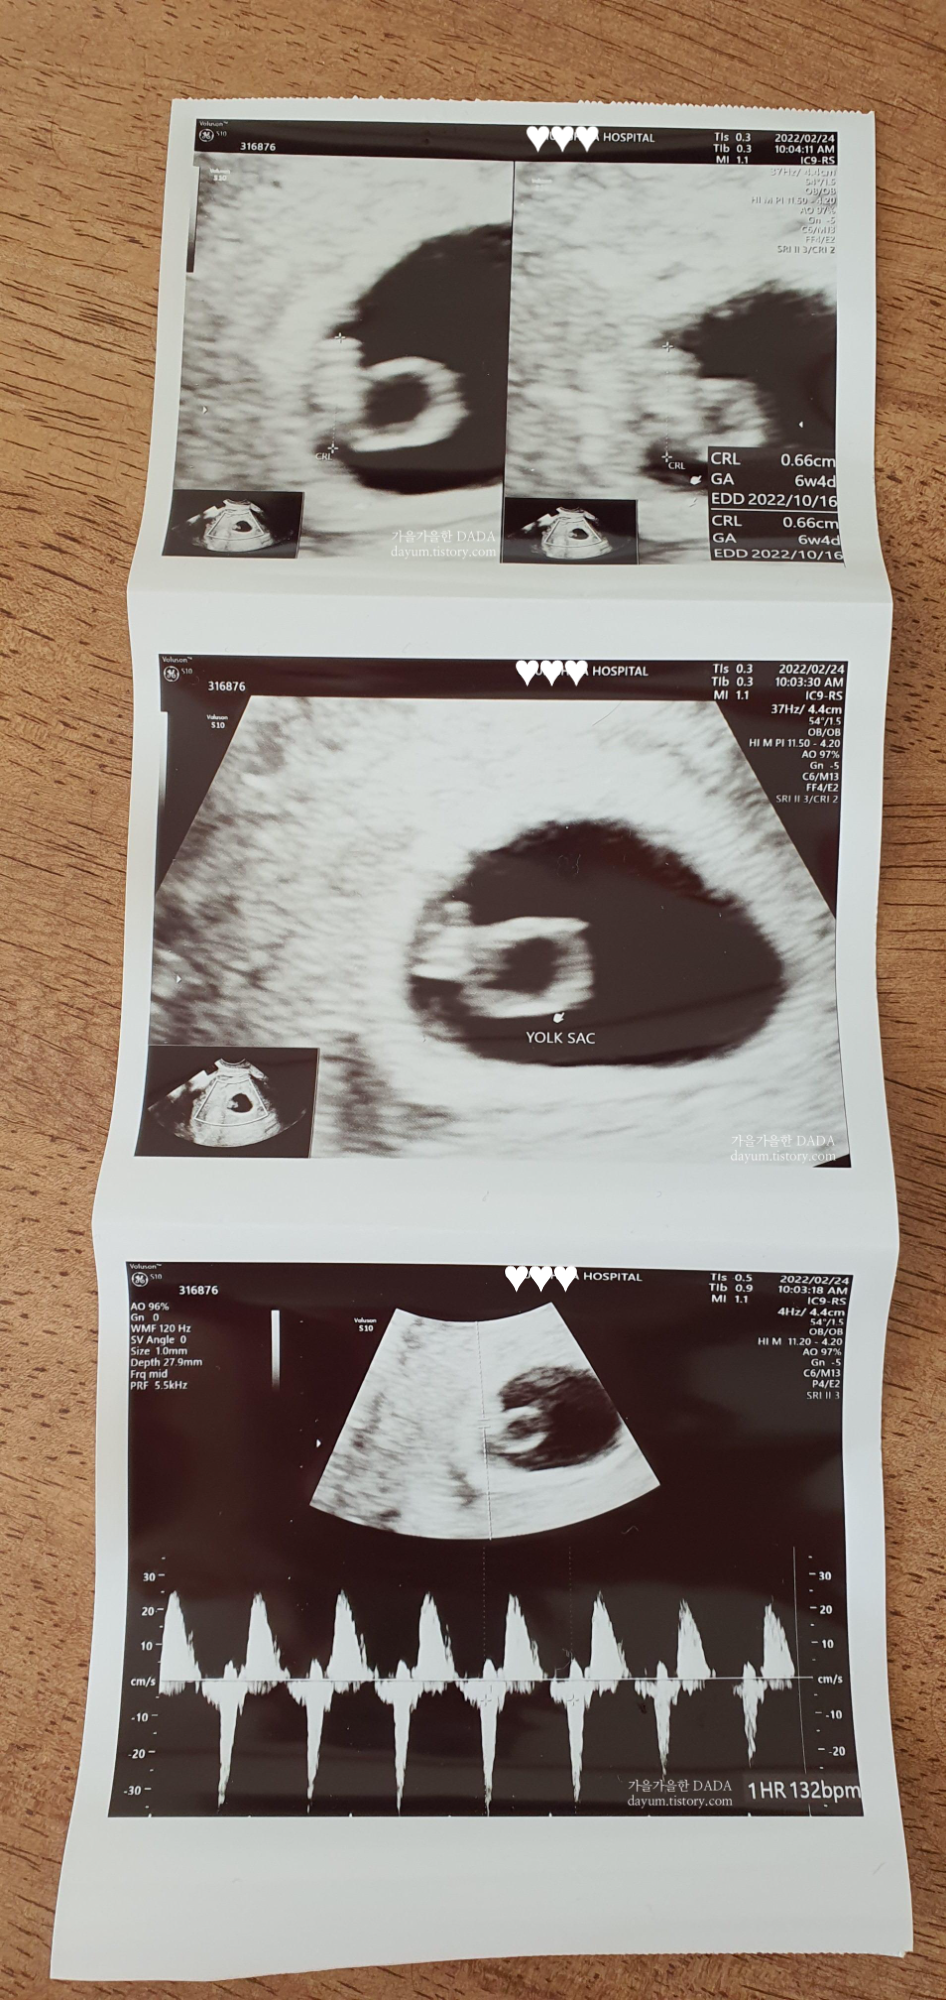

암튼, 그랬는데! 오늘이 6주1일차 였는데 초음파를 보고나서 6주4일로 바뀌었다.

출산예정일은 2022.10.16으로 바뀌었고 이제 바뀔일은 없을 거라고 하셨다.

반지링처럼 생긴 저건 난황이고 앞에 매달려 있는 애가 아기라고 한다.

오늘은 아기집과 난황 정도만 확인 할 수 있을 줄 알았는데 심장소리도 듣고 왔다.

132bpm으로 정상범위내에 있다고 한다.